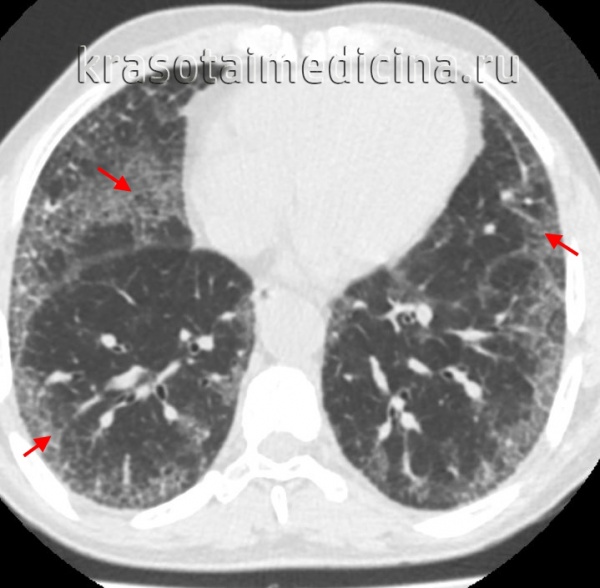

КТ ОГК. Интерстициальная пневмония, участки «матового стекла» (красная стрелка) и ретикулярные изменения.